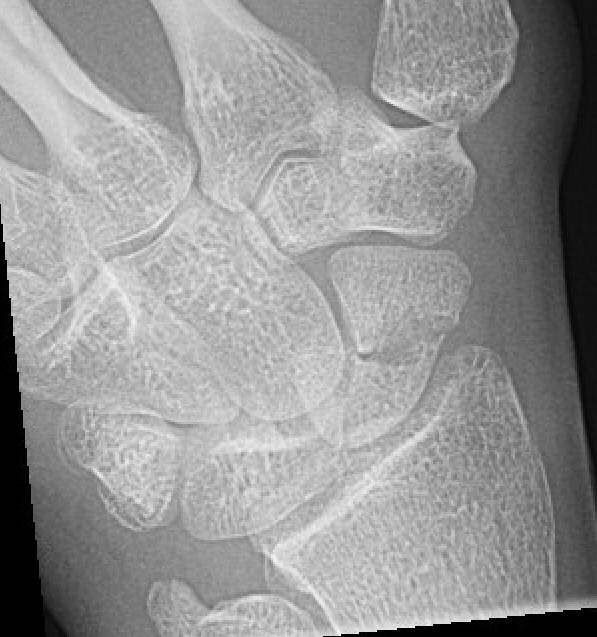

Midjefrakturer i skafoideum. Båda behandlade med gips, andra bilden läkte inte, opererades sedan